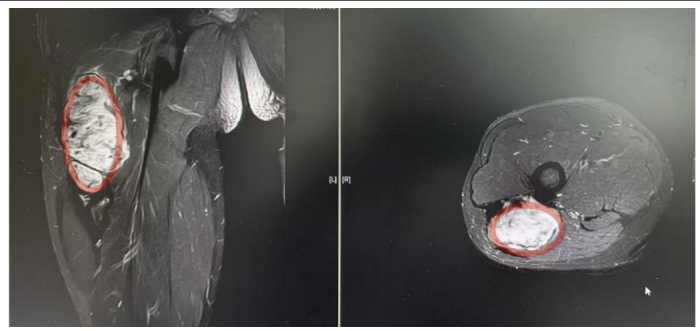

术前影像:红色标记部分为侵袭性纤维瘤

“患者入院后MR检查提示恶性肿瘤可能,肿块约10*2*2CM大小,经B超引导下行穿刺活检,病理提示:侵袭性纤维瘤病。”据手足显微外科副主任医师曾驰介绍,由于肿块较大,无法保守治疗,在完善术前准备后行瘤体切除术,手术顺利,术后患者恢复良好。